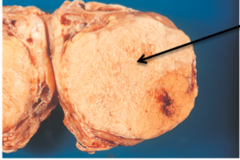

myocardial necrosis coagulative

Front

disease? type of necrosis

Back